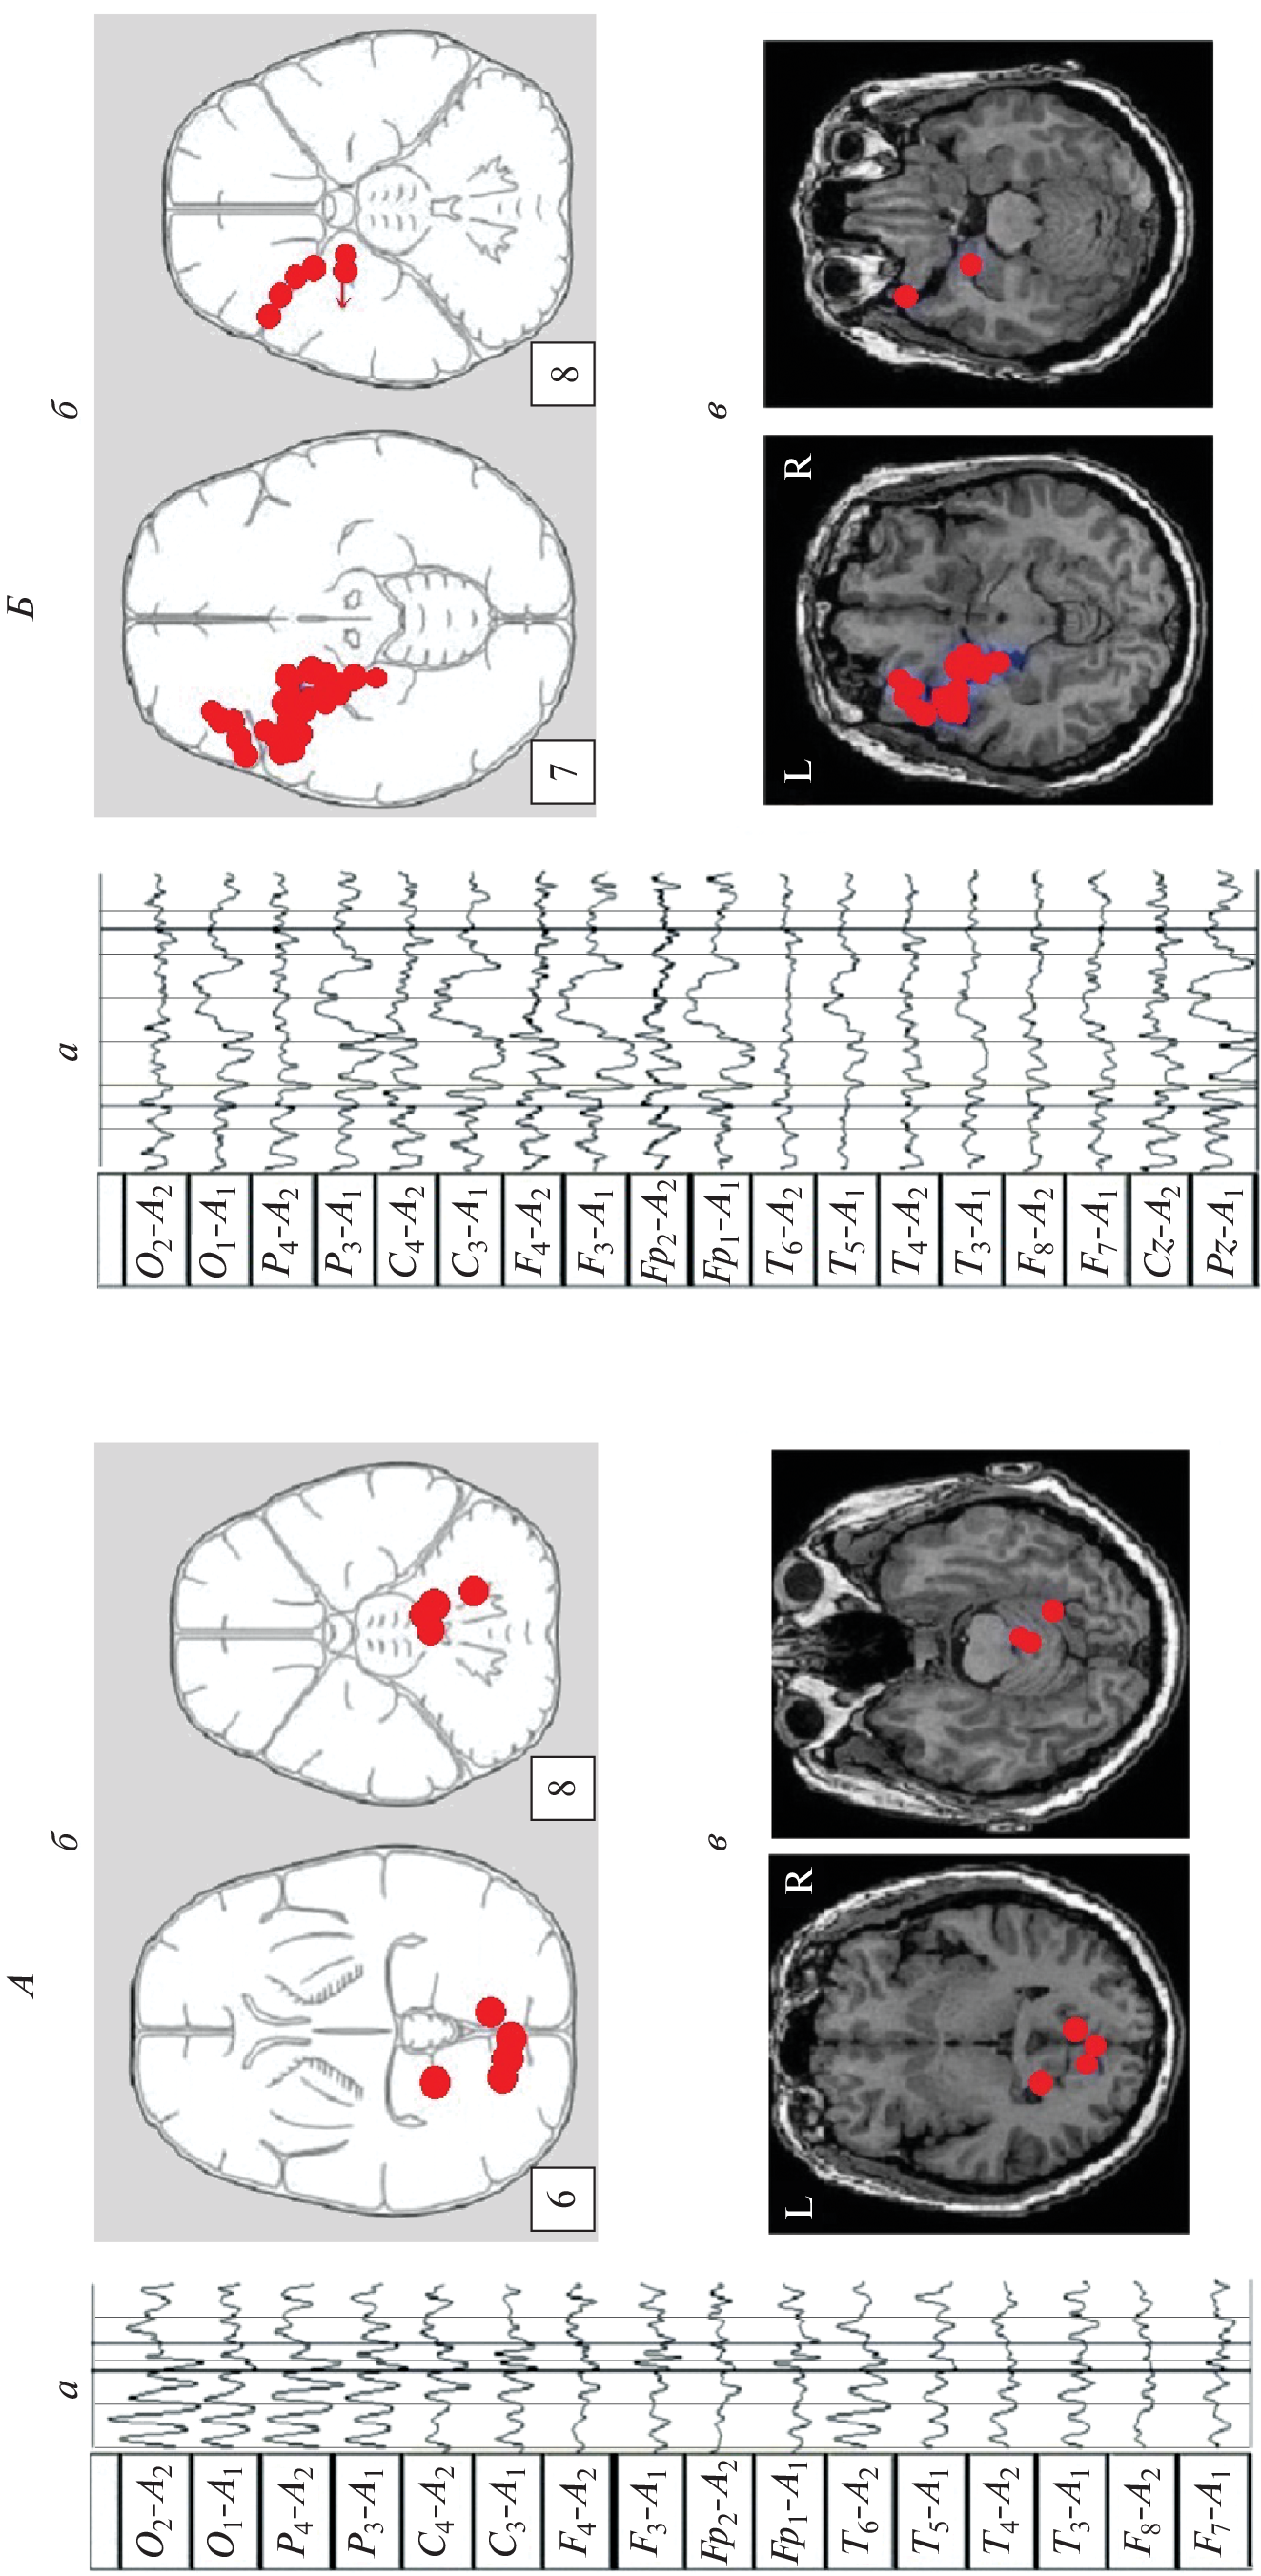

We studied the features of EEG and visual memory processes in 27 patients with a mediobasal regions extracerebral tumor of right and left hemispheres. According to neuroimaging (MRI) and morphometry, the degree of hippocampus involvement in pathological process was assessed. The predominant concentration of irritative-epileptiform signs in the affected hemisphere, as well as the presence of atypical alpha-rhythm episodes in the tumor projection zone, were classified as EEG markers of tumor compressive effect on the hippocampus. Signs of non-identical involvement of the right and left hippocampi in the pathological process were found in the form of a predominance of irritative signs in the left hemisphere throughout the group as a whole. Equivalent dipole sources (EDS) of atypical alpha rhythm are more confined to hippocampal structures than irritative EEG patterns. Neuropsychological testing of visual memory did not reveal significant disturbances in memory processes at this stage of the disease.

- Болдырева Г.Н. Атипичные формы церебральной альфа-активности при поражении регуляторных структур мозга человека // Физиология человека. 2018. Т. 44. № 3. С. 14. Boldyreva G.N. Atypical forms of cerebral alpha activity when human brain regulatory structures are damaged // Human Physiology. 2018. V. 44. № 3. P. 246.

- Болдырева Г.Н., Шарова Е.В., Коптелов Ю.М. и др. Исследование генеза патологических паттернов ЭЭГ при опухолевом и травматическом поражении мозга человека // Физиология человека. 2005. Т. 31. № 1. С. 24. Boldyreva G.N., Sharova E.V., Koptelov Yu.M. et al. Study of the genesis of pathological EEG patterns in tumor and traumatic lesions of the human brain // Human Physiology. 2005. V. 31. № 1. P. 18.

- Фролов А.А., Болдырева Г.Н., Коптелов Ю.М. Поиск источников патологической альфа-активности ЭЭГ человека при поражении лимбических структур // Журн. высш. нерв. деят. им. И.П. Павлова. 1998. Т. 48. № 4. С. 687. Frolov A.A., Boldyreva G.N., Koptelov Yu.M. [Sources of pathological EEG alpha-activity in patients with lesions of limbic structures] // Zh. Vyssh. Nerv. Deiat. Im. I.P. Pavlova. V. 48. № 4. P. 687.